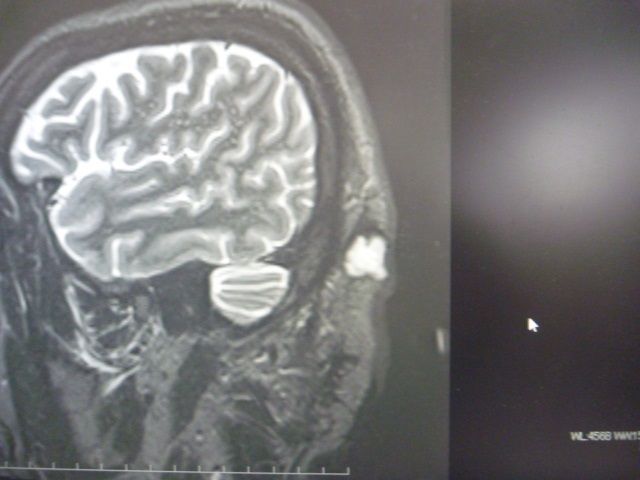

º£Æü¸åƬÉô¤ÎMRI»£±Æ¤Ë¹Ô¤Ã¤Æ¤¤Þ¤·¤¿¡£

²èÁü¤ò¸«¤¿½Ö´Ö¤Ë¡Ö¤Ç¤«¤Ã¡ª¡×¤Ã¤Æ¸À¤¦¤°¤é¤¤

Â礤Êʪ¤¬¼Ì¤Ã¤Æ¤¤¤Æ

¤Á¤ç¤Ã¤ÈÂ礲᤮¤ë¤Î¤Î¤È

¼è¤ê½Ð¤¹¤Î¤Ë¤âƬ¤òÀÚ¤ëÈϰϤ¬Â礤¯

½Ð·ì¤¬Â¿¤¤¤ÈͽÁÛ¤µ¤ì¤ë»ö¤ä

Ƭ³¸¹ü¤Ë¶á²á¤®¤ë¤Î¤È

´¶À÷¾É¤Î¥ê¥¹¥¯¤¬Â¿¤¤¤Î¤Ç

¥Á¡¼¥à¤ÇºîÀï²ñµÄ¤ò¤¹¤ë¤é¤·¤¤¡Ä

¼ê½Ñ¤âǯÌÀ¤±Á᡹¤Ë¤Ê¤ë´¶¤¸¤Ç¤¹¡£

¤â¤¦¡Ä¤È¤ó¤À¥¯¥ê¥¹¥Þ¥¹¥×¥ì¥¼¥ó¥È¤Ç¤·¤¿¡£